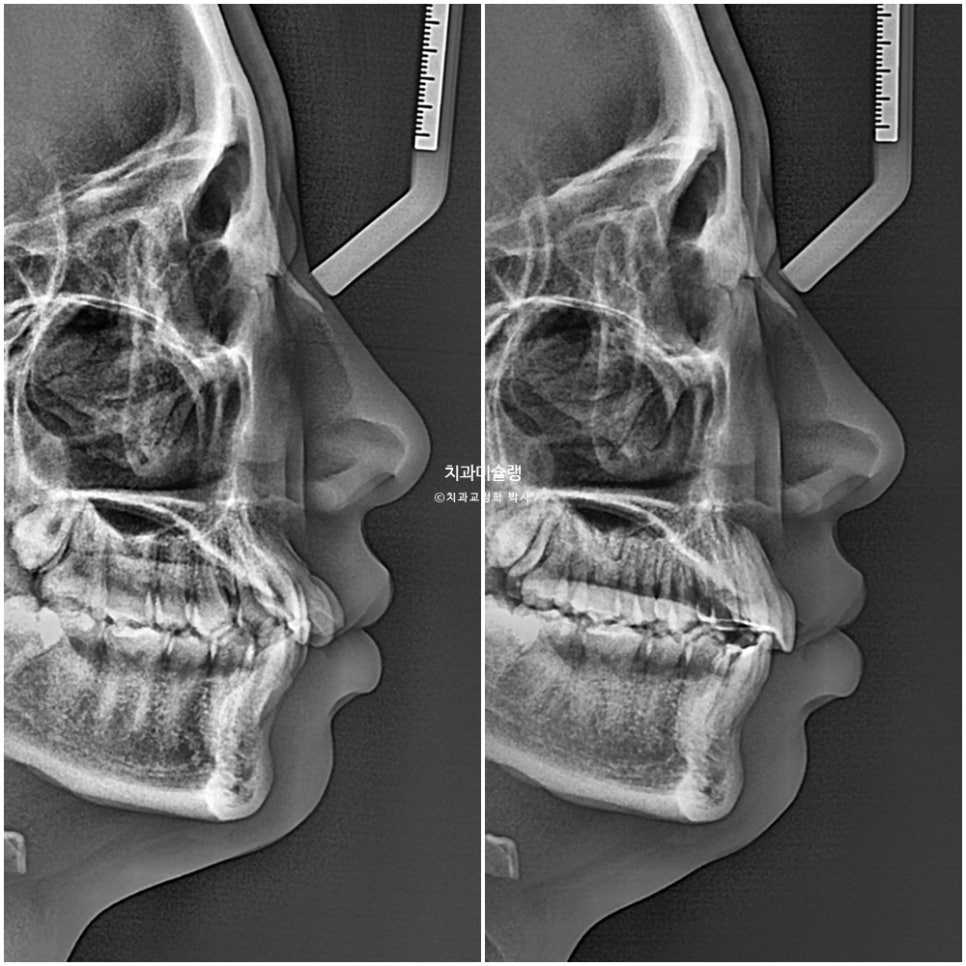

윗니 몇개가 뻗쳐있기는 하나 초진 안모에서 입이 안 다물어질 정도의 돌출은 아니었습니다.

45도 측모 에서는 웃을때 약간의 돌출감은 여전히 남았으나 환자분은 만족하셨죠.

교정 전후 입매 변화는 없습니다.